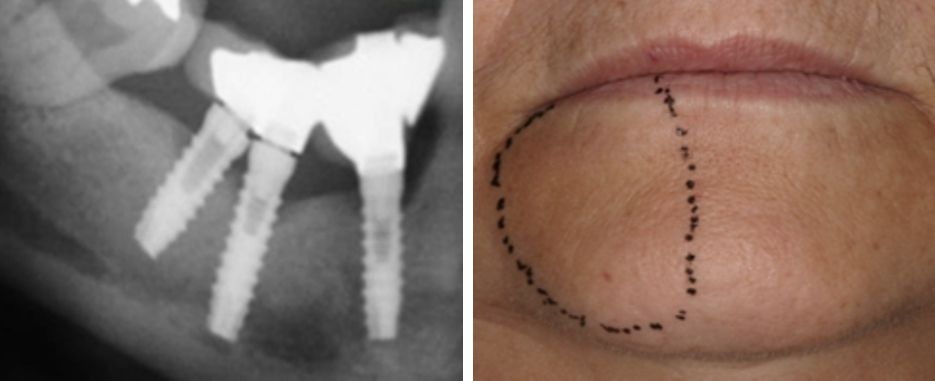

Lo normal es que se recupere la sensibilidad de la zona y vuelva a índices normales en un periodo de tiempo de 2 a 6 meses, desapareciendo con el tiempo todas sus molestias. Para ver la evolución el dentista puede dibujar en cada visita la zona afectada sobre tu piel y hacer una fotografía; de este modo podréis saber si la pérdida de sensibilidad se está recuperando.